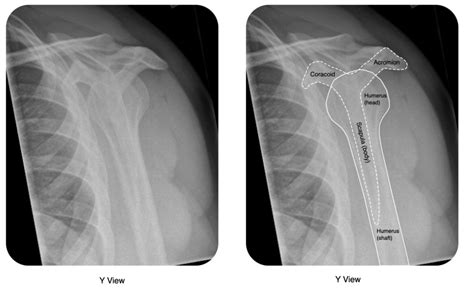

Dean Jones Blog